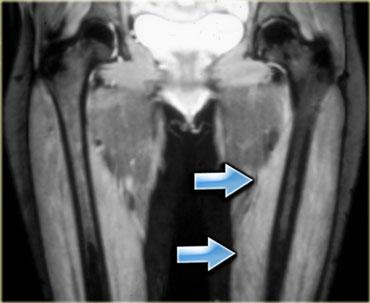

Hình bên trái là một ví dụ, lưu ý các thay đổi viêm ở các cơ lớn vùng mông.

Sau khi ngừng thuốc, đau cơ sẽ biến mất trong khoảng 2 tuần, tuy nhiên MRI vẫn còn cho thấy bất thường cho đến khoảng một tháng sau đó.

Thời điểm tốt nhất để chụp MRI theo dõi là khoảng 6 tuần sau khi ngừng thuốc.

Đây là bệnh nhân cao tuổi có tăng cholesterol máu được chỉ định dùng Lipitor.

Bệnh nhân xuất hiện đau nhức cơ, CPK tăng nhẹ.

Các thay đổi khá tinh tế, chúng ta thấy các ổ tụ dịch quanh mạc cơ, ở rìa ngoài của cơ (ngoại mạc cơ).

Ngoài ra còn có thay đổi da tối thiểu.